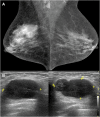

Breast metastases from extramammary cancers are rare and usually related to poor prognosis. The extramammary tumours most frequently exhibiting breast metastases are melanoma, lymphomas, ovarian cancer, lung and neuroendocrine tumours, and sarcomas. Owing to the lack of reliable and specific clinical or radiological signs for the diagnosis of breast metastases, a combination of techniques is needed to differentiate these lesions from primary breast carcinoma or even benign breast lesions. Multiple imaging methods may be used to evaluate these patients, including mammography, ultrasound, MRI, CT and positron emission tomography CT. Clinical and imaging manifestations are varied, depend on the form of dissemination of the disease and may mimic primary benign and malignant breast lesions. Haematologically disseminated metastases often develop as a circumscribed mass, whereas lymphatic dissemination often presents as diffuse breast oedema and skin thickening. Unlike primary carcinomas, breast metastases generally do not have spiculated margins, skin or nipple retraction. Microlobulated or indistinct margins may be present in some cases. Although calcifications are not frequently present in metastatic lesions, they occur more commonly in patients with ovarian cancer. Although rare, secondary malignant neoplasms should be considered in the differential diagnosis of breast lesions, in the appropriate clinical setting. Knowledge of the most common imaging features can help to provide the correct diagnosis and adequate therapeutic planning.